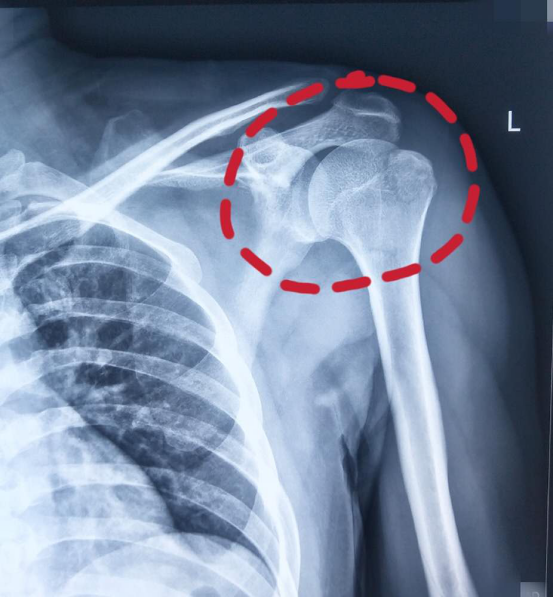

左侧肱骨近端骨折

左肱骨大结节撕脱性骨折

左肱骨近端粉碎性骨折(原创,有图)

肱骨近端骨折